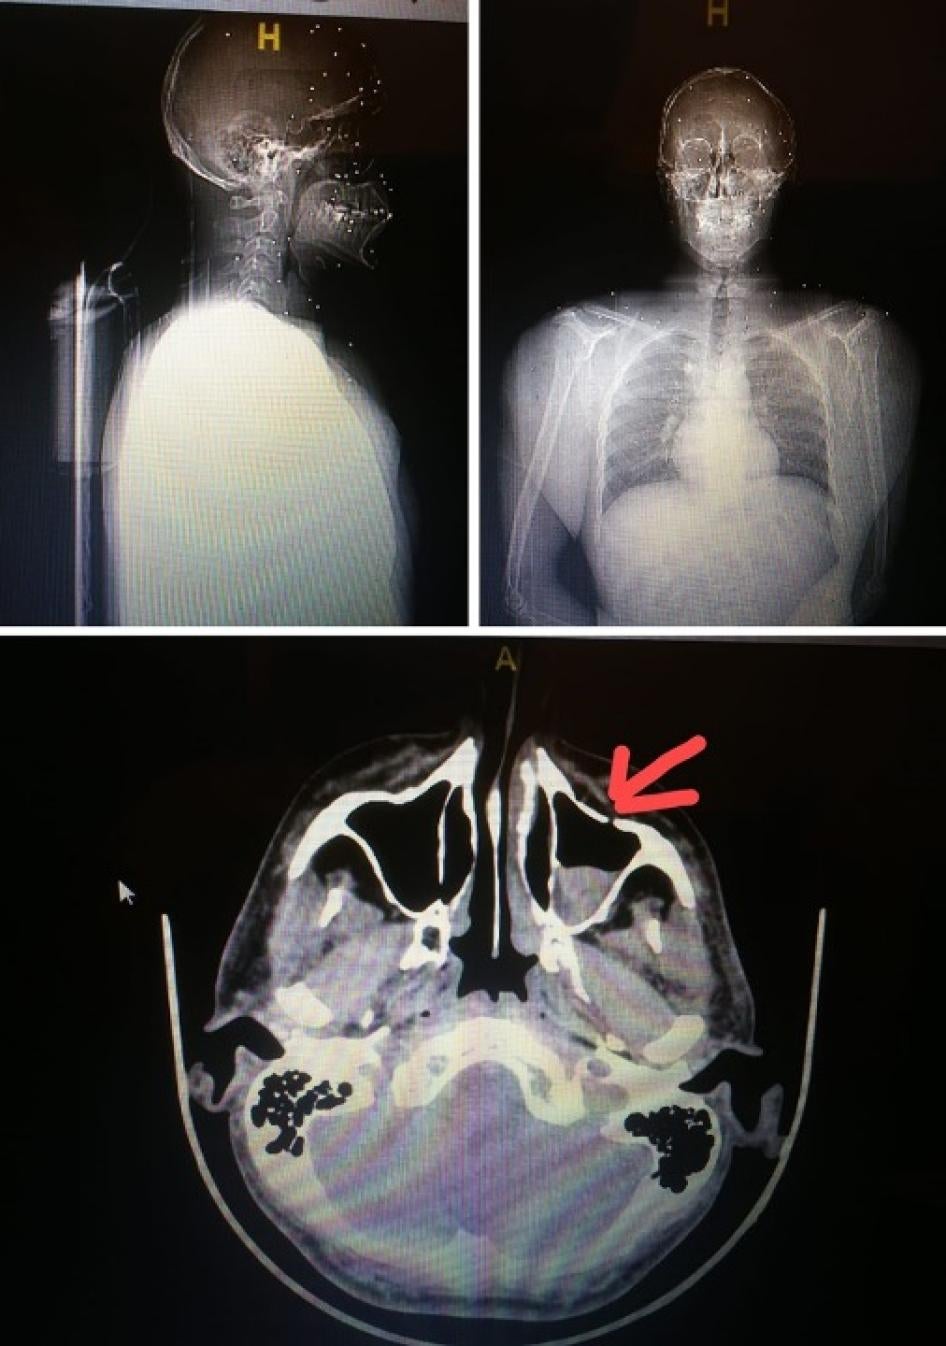

For the first time in Lebanon, Human Rights Watch documented several instances of Lebanese security forces using shotgun-fired metal pellets that wounded people. In some cases, security forces fired toward people’s upper bodies, including the head and face. Human Rights Watch reviewed medical records and X-rays, spoke to 3 victims and 4 doctors who treated them, and analyzed a pellet recovered from one person’s body, as well as a photograph of another. Additionally, the “White Shirts” doctors shared anonymized medical records of 13 patients seriously injured by the metal pellets.

Another doctor shared the anonymized X-rays of a patient who was wounded by dozens of pellets. The doctor said that the number of pellets and the fact that they punctured the patient’s scalp indicate that security forces shot at the person’s face from a very short distance. The pellets embedded under the sinus in the skull and in the protester’s eye, the doctor said.

The same doctor treated another protester who was shot with a metal pellet in the neck. The doctor said that the pellet tore an artery in the neck, punctured the lung, and finally lodged in the protester’s spinal cord. The doctor said that, had the pellet been one millimeter closer to his spinal cord, the protester would have been permanently paralyzed.